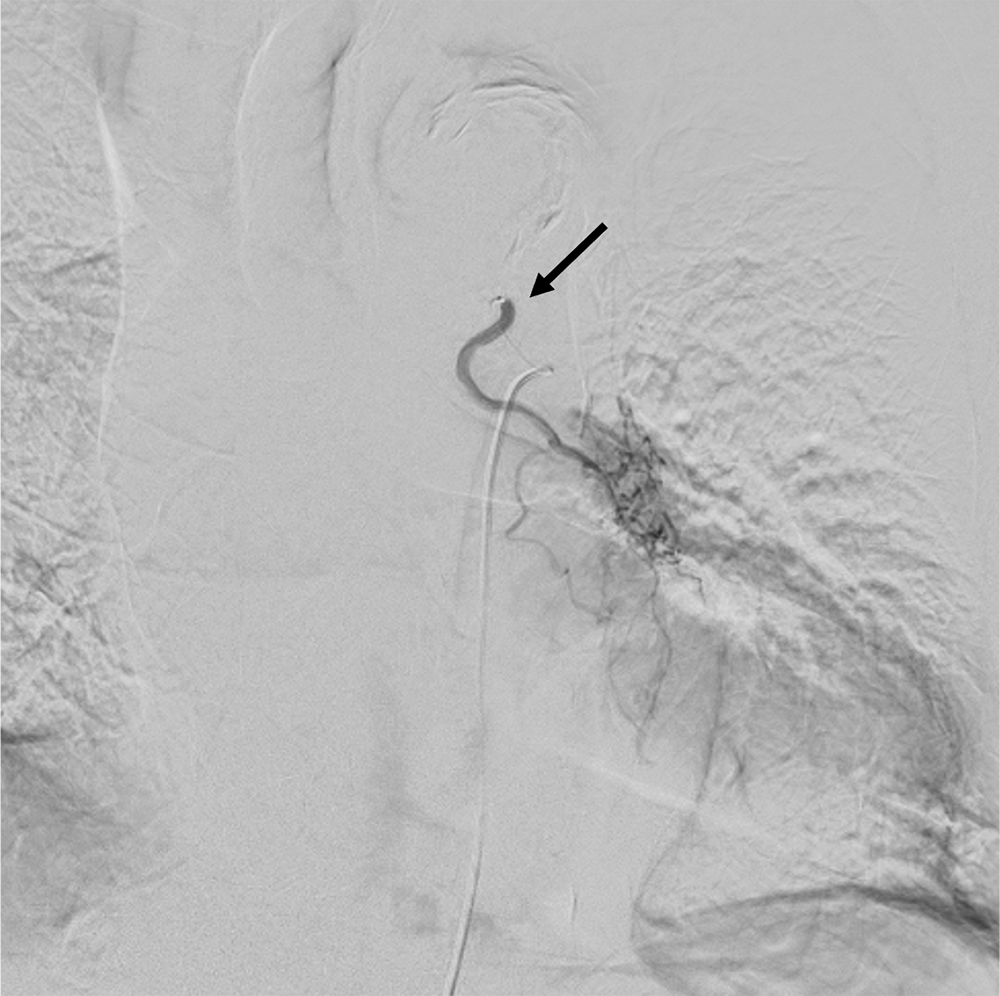

症例は左膿胸に対し術後の既往がある患者。少量の喀血が継続することを主訴に呼吸器内科を受診し、造影CTが施行された。左肺下葉にはすりガラス陰影とconsolidationがみられ、喀血の吸い込み像と思われた。左気管支動脈は拡張していたが、起始部で高度狭窄が疑われた。BAE施行目的に当院放射線科に紹介された。

今回は臨床的に左気管支動脈が原因として疑われていたが、起始部が極めて細径であった。カテーテル治療が困難と思われたが術前造影CTを施行し、thin sliceにて起始部のレベル・分岐方向を同定することができた。このことで必要十分な塞栓術が施行され、治療を完遂することができた症例である。